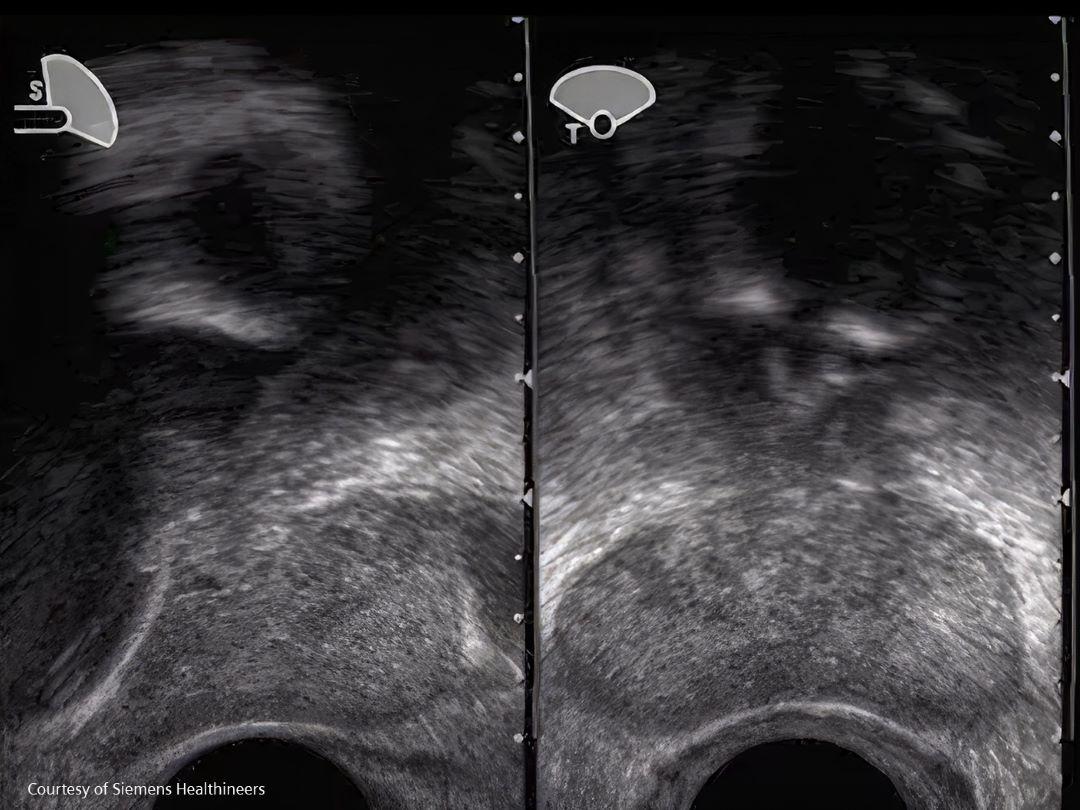

Diagnosis and Staging

What if a doctor suspects a patient might have prostate cancer?

During diagnosis, a patient will be asked about any symptoms as described above and about possible risk factors including his family history. In case of any suspicion, the doctor might order some tests.